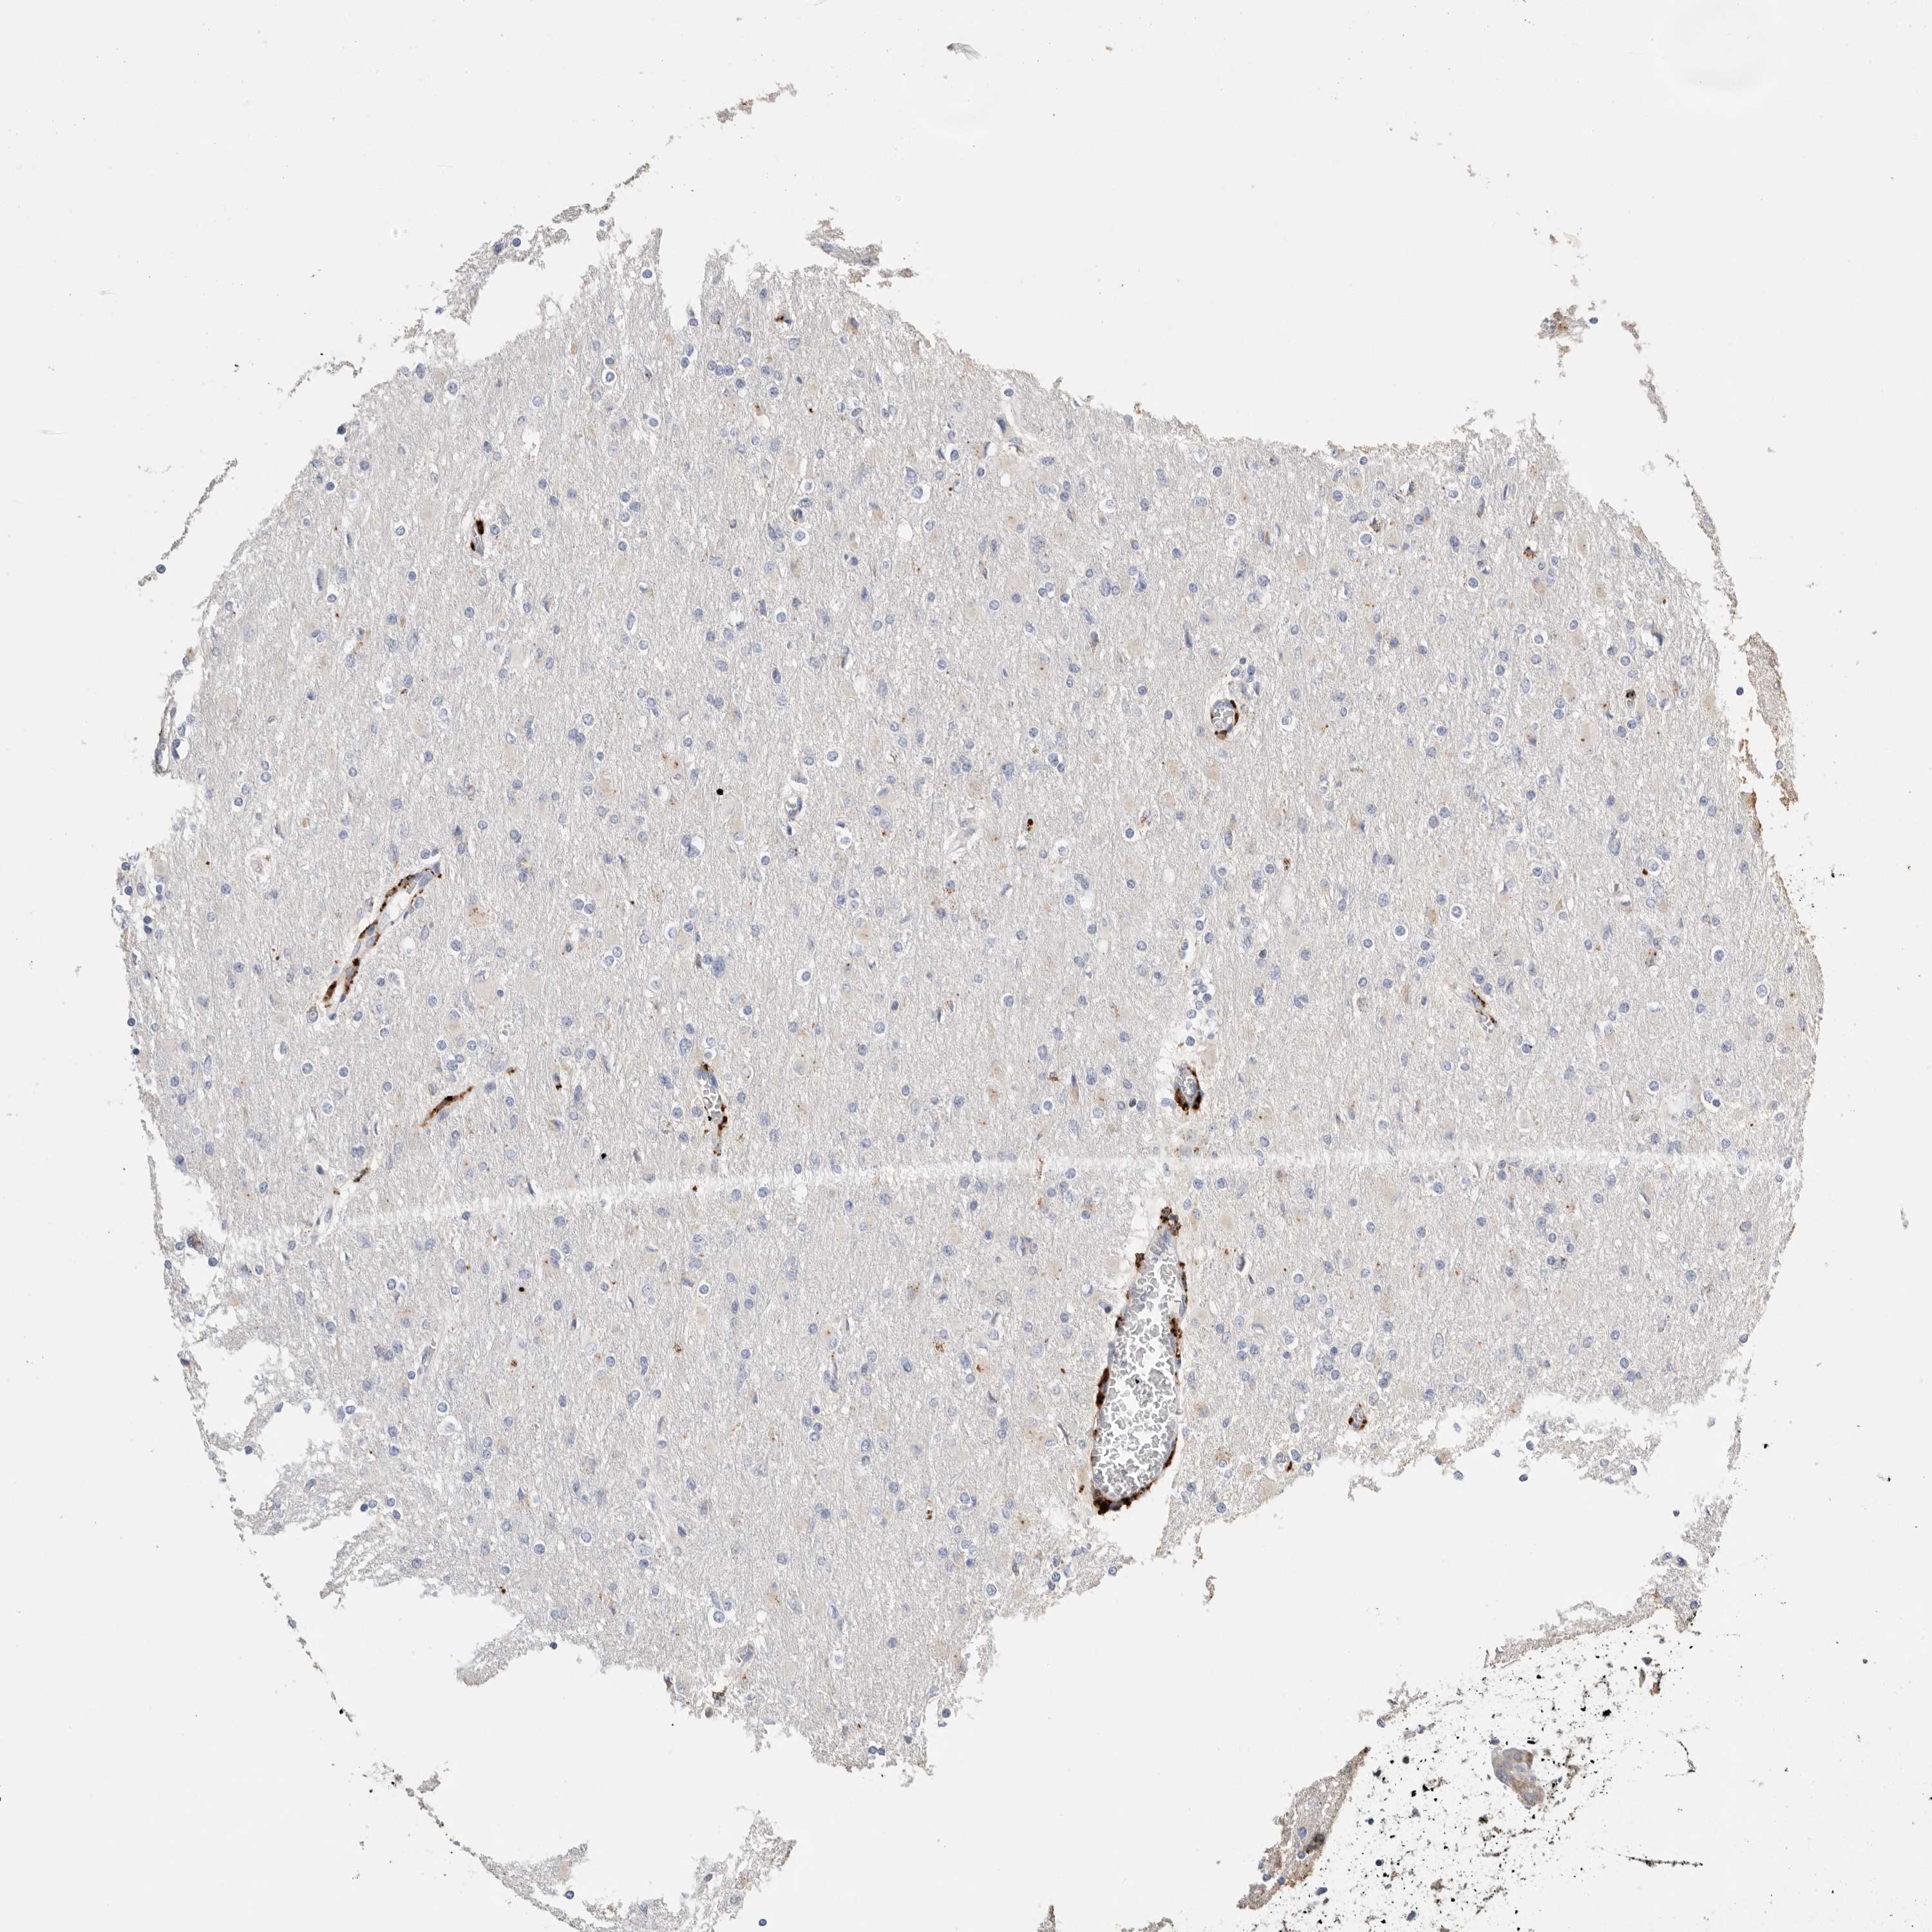

GLIOMA - Protein expressioni

A mouse-over function shows sample information and annotation data. Click on an image to view it in a full screen mode. Samples can be filtered based on level of antibody staining by selecting one or several of the following categories: high, medium, low and not detected. The assay and annotation is described here.

Note that samples used for immunohistochemistry by the Human Protein Atlas do not correspond to samples in the TCGA dataset.

Antibody stainingi

Antibody staining in the annotated cell types in the current human tissue is reported as not detected, low, medium, or high, based on conventional immunohistochemistry profiling in selected tissues. This score is based on the combination of the staining intensity and fraction of stained cells.

Each image is clickable and will lead to virtual microscopy that enables deeper exploration of all samples and also displays staining intensity scores, fraction scores and subcellular localization as well as patient and tissue information for each sample.

Antibody HPA025226

Antibody CAB019296

Staining

High

Medium

Low

Not detected

Intensity

Strong

Moderate

Weak

Negative

Quantity

>75%

75%-25%

<25%

None

Location

Nuclear

Cytoplasmic/membranous

Cytoplasmic/membranous,nuclear

Glioma, malignant, High grade

Glioma, malignant, Low grade